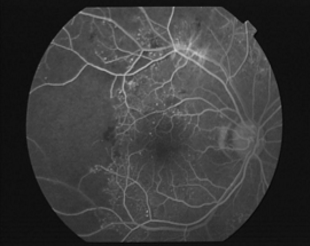

视神经病变